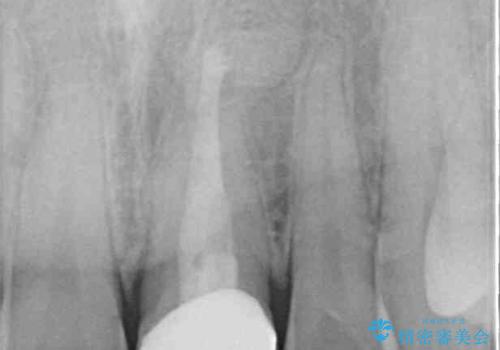

ぶつけて変色した前歯 オールセラミッククラウン治療

- 以前ぶつけて神経を取り除いてから、徐々に変色してきた前歯が気になるとのことで来院された患者様です。

神経を取り除いた歯の変色はホワイトニングでは十分に改善できないため、オールセラミッククラウンにて補綴治療を行うこととしました。

定期的にホワイトニングをされていることや、前歯の歯列が左右非対称であることから、色合いや形態の修正が多くなることが予想されたため、オーダーメイドタイプのグレードを選択していただき、治療を進めて行くこととしました。

予想通り色と形の修正が多く必要となりましたが、最終的には納得のいく仕上がりとなりました。